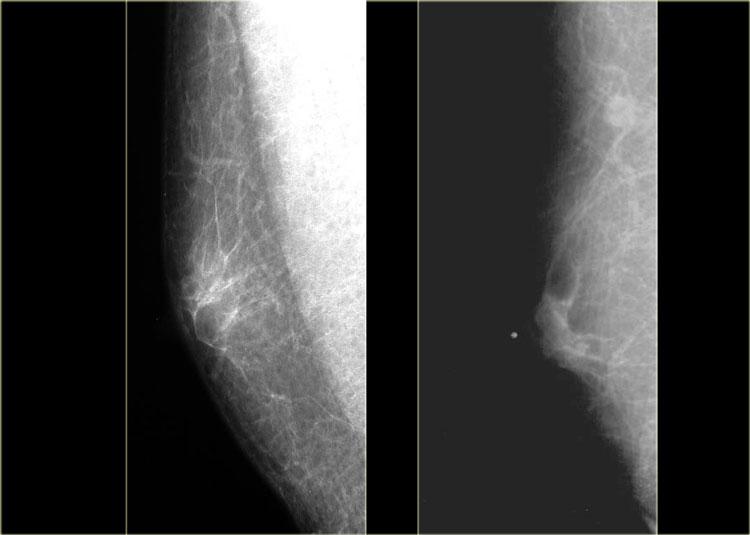

Bên trái là hai ví dụ về nhũ ảnh nam giới bình thường.

Hình bên trái cho thấy da bình thường, núm vú và một lượng nhỏ mô liên kết phía sau núm vú.

Hình bên phải cho thấy nhiều mô liên kết hơn một chút, nhưng vẫn trong giới hạn bình thường.